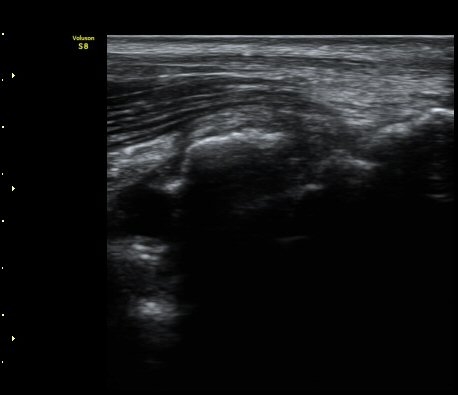

[ÆÈ²ÞÄ¡] ÆÈ²ÞÄ¡ °üÀý³» À¯¸®Ã¼¿¡ ÀÇÇÑ ÆÈ²ÞÄ¡ ÅðÇ༺ °üÀý¿°

³²ÀÚ/ 44¼¼

ÁÖÁõ»ó

ÆÈ±ÀÄ¡ ÅëÁõ

ÃÊÀ½ÆÄ °Ë»ç